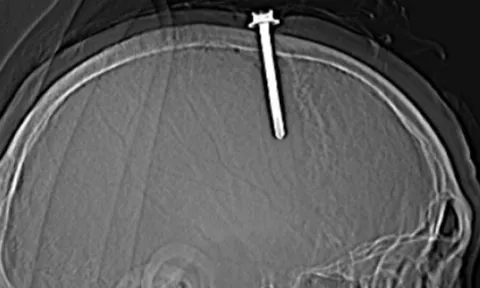

Ngày 25/7, Bệnh viện Hữu nghị Việt Nam - Cuba Đồng Hới (Quảng Bình) cho biết, các bác sĩ vừa phẫu thuật thành công để đưa dị vật là một cây đinh ra khỏi não một bệnh nhân 66 tuổi